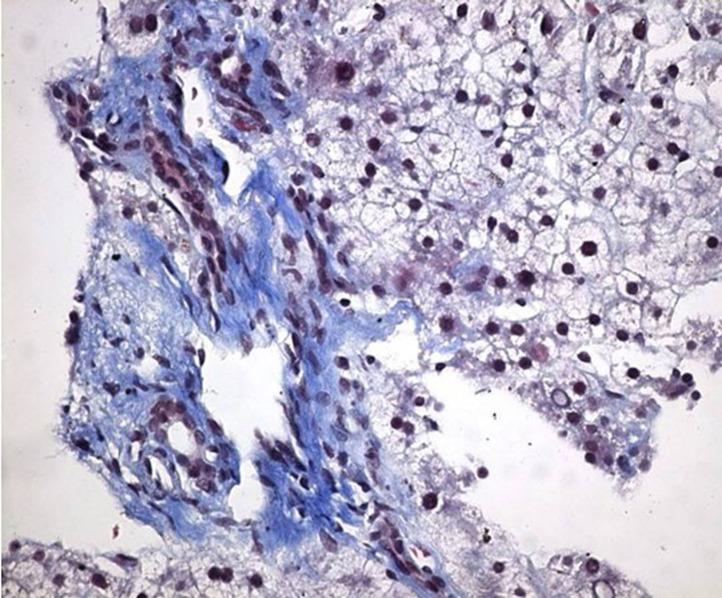

Squamous cell carcinomas of esophagus are responsible for more than 80% of esophageal malignancies in Turkey. Idiopathic portal hypertension is a rare underlying cause of esophageal variceal bleeding. In such cases, detection of concomitant esophageal squamous cell cancer is also a rare occurrence. We report an unusual case of bleeding esophageal varices secondary to idiopathic portal hypertension associated with esophageal squamous cell cancer. To our knowledge, until now, there have been no reported cases of esophageal variceal bleeding due to idiopathic portal hypertension associated with esophageal squamous cell cancer. This case report demonstrates the two different conditions which may cause esophageal bleeding and there may be an association between idiopathic portal hypertension and esophageal squamous cell cancer.

在土耳其,食管鳞状细胞癌占食管恶性肿瘤的80%以上。特发性门静脉高压是食管静脉曲张出血的罕见潜在病因。在这些病例中,同时检测到食管鳞状细胞癌的情况也很少见。我们报告一例罕见病例,特发性门静脉高压继发食管静脉曲张出血并伴有食管鳞状细胞癌。据我们所知,迄今为止,尚无特发性门静脉高压合并食管鳞状细胞癌导致食管静脉曲张出血的病例报道。本病例报告展示了可能导致食管出血的两种不同情况,且特发性门静脉高压与食管鳞状细胞癌之间可能存在关联。